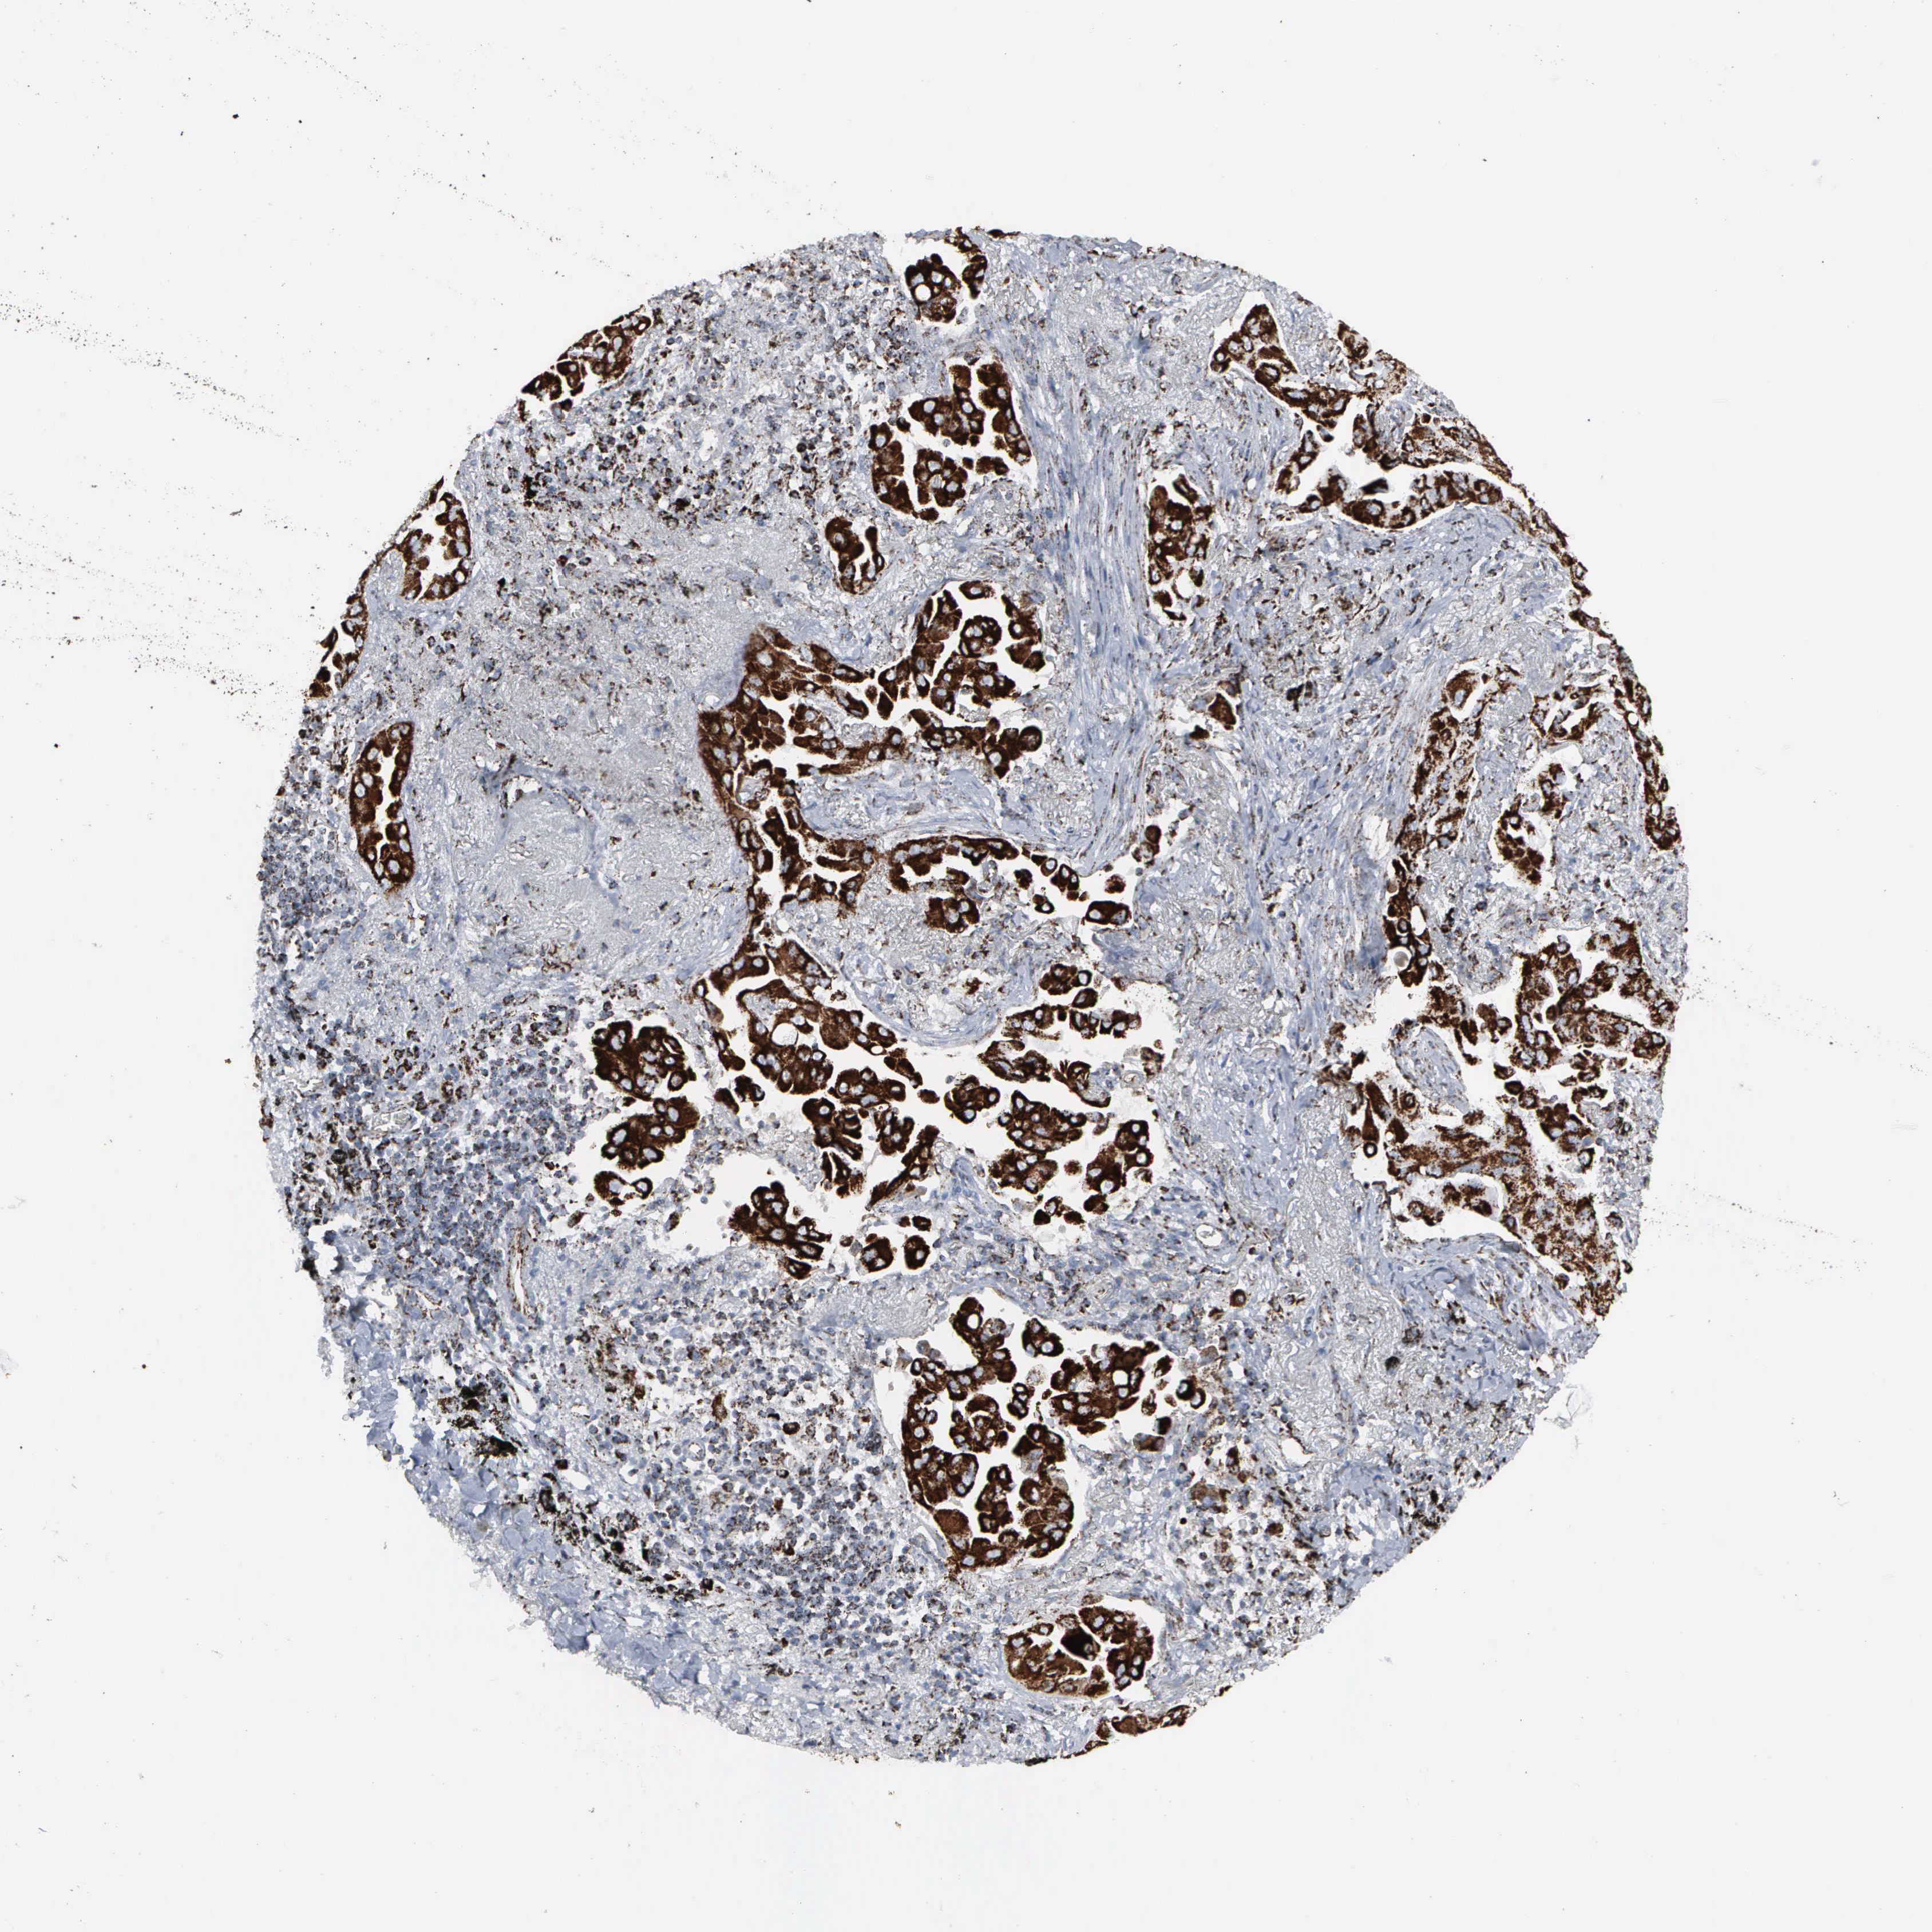

CANCER LUNG CANCER Show tissue menu

Lung cancer

Human cancer

Lung adenocarcinoma

Lung squamous cell carcinoma